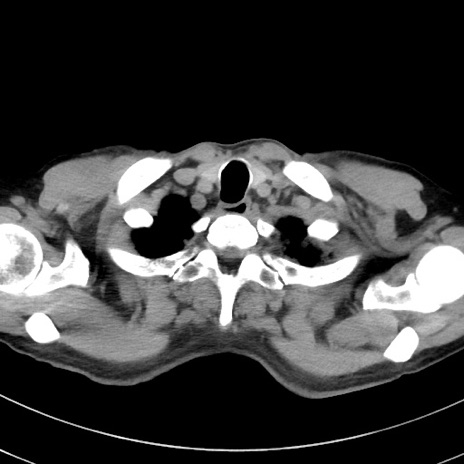

症例38(横断像)

【症例】70歳代 男性

【主訴】腹痛・嘔吐

【現病歴】昨晩より、嘔吐・腹痛あり。今朝になっても嘔吐あり。来院。

【既往歴】心臓バイパス手術、開腹胆摘、腸閉塞

【身体所見】BP 107/71mmHg、HR 116/min、腹部:平坦、軟、下腹部に軽度圧痛あり。反跳痛なし。

【データ】WBC 15100、CRP 0.32